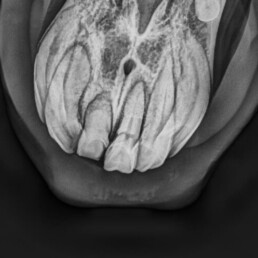

- röntgenologische Untersuchung zur Bestätigung der Verdachtsdiagnose EOTRH

- deutliche Befunde erkennbar

- resorptive und hyperzementotische Veränderungen an den Schneidezähnen/Schneidezahnwurzeln